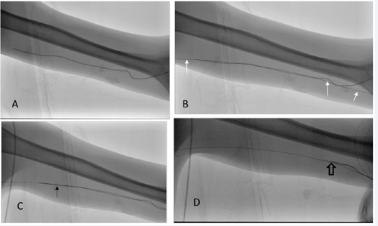

A 26 year male had a PICC (Vaxcel PASV, 4 fr single lumen polyurethrane, Navilyst, Marlborough, Mass) line placed in left arm to receive a 2 week course of chemotherapy for malignant fibrous histiocytoma, but the PICC line became stuck in left brachial vein during attempted removal. Despite one instillation of r-tPA (2 mg in 5ml normal saline), left to act overnight, the catheter remained stuck. Under combined ultrasound and fluoroscopic guidance, a venipuncture of the thrombosed basilic vein was performed to introduce a small 0.018 inch diameter hydrophilic guidewire (V-18 Control wire, Boston Scientific) and advance a 3 fr catheter (pulse-spray Catheter 2cm spray infusion length, Angiodynamics) into the same vein to instill 2mg r-tPA alongside the imbedded PICC line (Figures 2 and 3).

Figure 3: Case 2: Fluoroscopic views of manipulations to remove imbedded PICC line: A: Left arm PICC line imbedded in left brachial/basilica vein. B: Guidewire (white arrows) passed alongside PICC line in thrombosed vein. C: 3 French pulse spray catheter (Angiodynamics) passed over guidewire allowing injection of small amounts of tPA into vein along outside of PICC line (arrow). D: 2 hours later, PICC line is easily removed (open arrow-just before complete removal) under fluoroscopic vision.

Two hours later the catheter was easily removed.